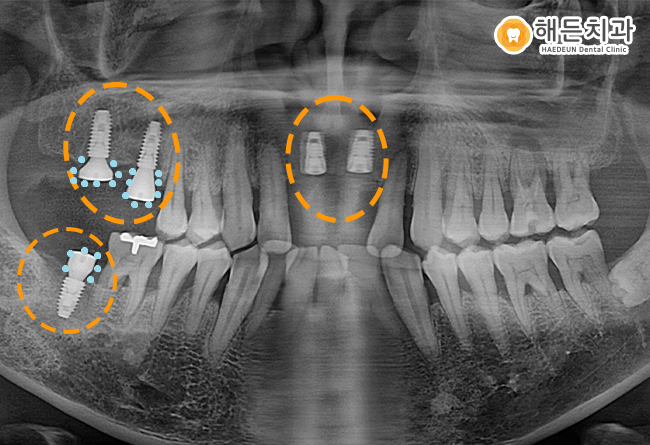

배방역치과 해든치과에서의 임플란트 식립 후 사진입니다.

임플란트는 치아 뿌리 역할을 하는 픽스처, 치아 머리 역할을 하는 크라운, 픽스처와 크라운을 연결하는 지대주

이렇게 3가지로 구성이 되어있는데요.

픽스처를 식립하고 픽스처가 잇몸뼈에 충분히 유착할 수 있도록

잇몸뼈의 상태에 따라 약 3~6개월 정도 기다린 후 상부 보철물인 크라운을 올려주게 됩니다.

현재 위의 파노라마 사진을 보시면 임플란트 픽스처만 식립되어 있는 상태인데요.

픽스처가 잇몸뼈에 잘 유착할 수 있도록 기다리는 동안

힐링 어버트먼트나 커버스크류라는 뚜껑을 픽스처 위에 체결한 후 기다리게 됩니다.

오른쪽 위아래 임플란트는 식립 후 하늘색 표시의 힐링 어버트먼트라는 뚜겅을 체결해놓은 상태이고

앞니 부분은 커버스크류라는 뚜껑을 체결하여 잇몸 속에 묻어놓은 상태입니다.

구강 내 상황에 따라 힐링 어버트먼트 혹은 커버스크류라는 뚜껑을 체결하게 되는데요.

잇몸뼈의 양이 충분하지 않고 잇몸의 상태가 좋지 않을 경우,

잇몸뼈와 픽스쳐가 더욱 잘 유착할 수 있도록 픽스처 위에 커버스크류를 체결하여

잇몸 안에 모든 식립 재료를 묻어 두게 됩니다.